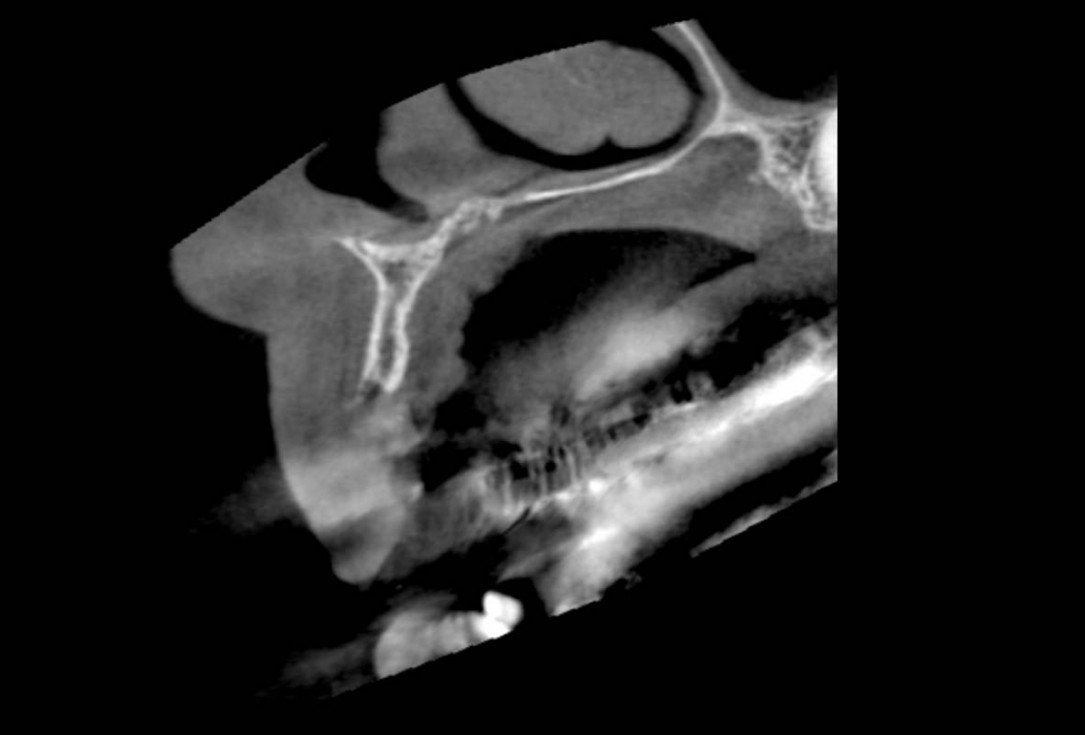

Initial CBCT scan - Fracture of left maxillary incisor and loss of buccal wall